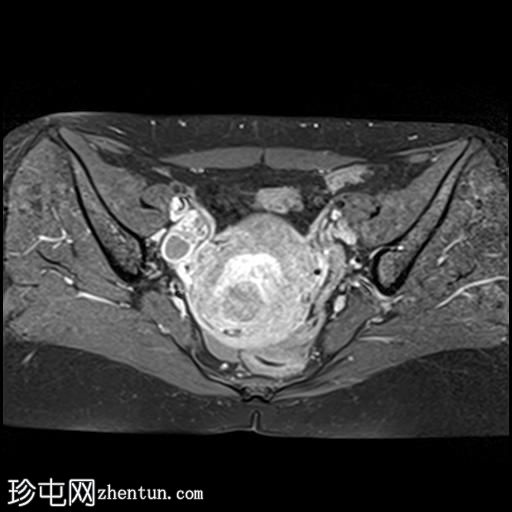

轴位

T2加权像

子宫增大,前倾后屈,可见多发大小不一、位置各异的壁内肌瘤(主要位于Figo 2、5和6区)。

一个边界清晰的带蒂宫腔内肿块经扩张的宫颈管脱出。T1加权像上呈等信号,T2加权像上呈中低信号,周围环绕着高信号的子宫内膜,静脉注射对比剂后呈明显不均匀强化。

双侧卵巢外观正常,可见小卵泡。

MRI 影像特征最符合带蒂子宫肌瘤经扩张的宫颈管脱垂,并伴有多个子宫肌瘤。